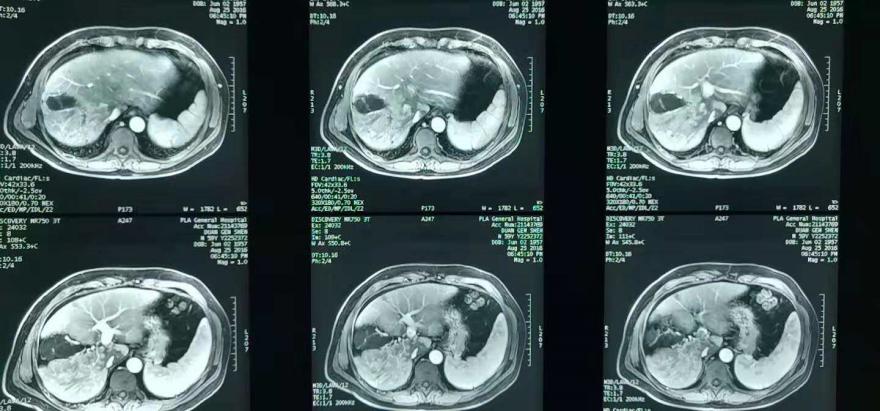

2016年8月16日,腹部MR显示,肝体积尚可,肝内见弥漫分布约3 mm以下短T2信号,肝右叶见多发约31、30、29 mm以下稍长T1、稍长T2异常信号影,DWI呈异常稍高信号,反相位图像病变信号及肝实质信号未见明显降低;动脉期病灶轻至中度不均匀异常强化,门静脉期和延迟期廓清。

肝门部门静脉、门静脉右支及主干见充盈缺损影,DWI呈高信号,动脉期轻度异常强化。 肝静脉、下腔静脉未见充盈缺损影。肝右叶及肝左内叶见多发约7 mm以下长T1、长T2信号,增强扫描未见强化。

肝内外胆管、胰管未见异常狭窄或扩张。脾脏增大,未见异常强化。胆囊、胰腺及双侧肾上腺未见异常,肝门及所见腹膜后未见明确肿大淋巴结(图1、图2)。

图1. 基线腹部MR表现